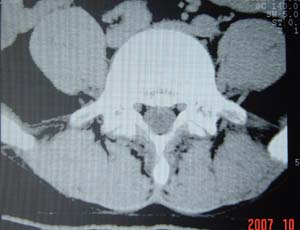

本人的片子,腰腿痛多年,时轻时重。请各位老师发表高见!

1.l4~5间盘膨出伴突出(中央型)

2.l5-s1后纵韧带钙化.